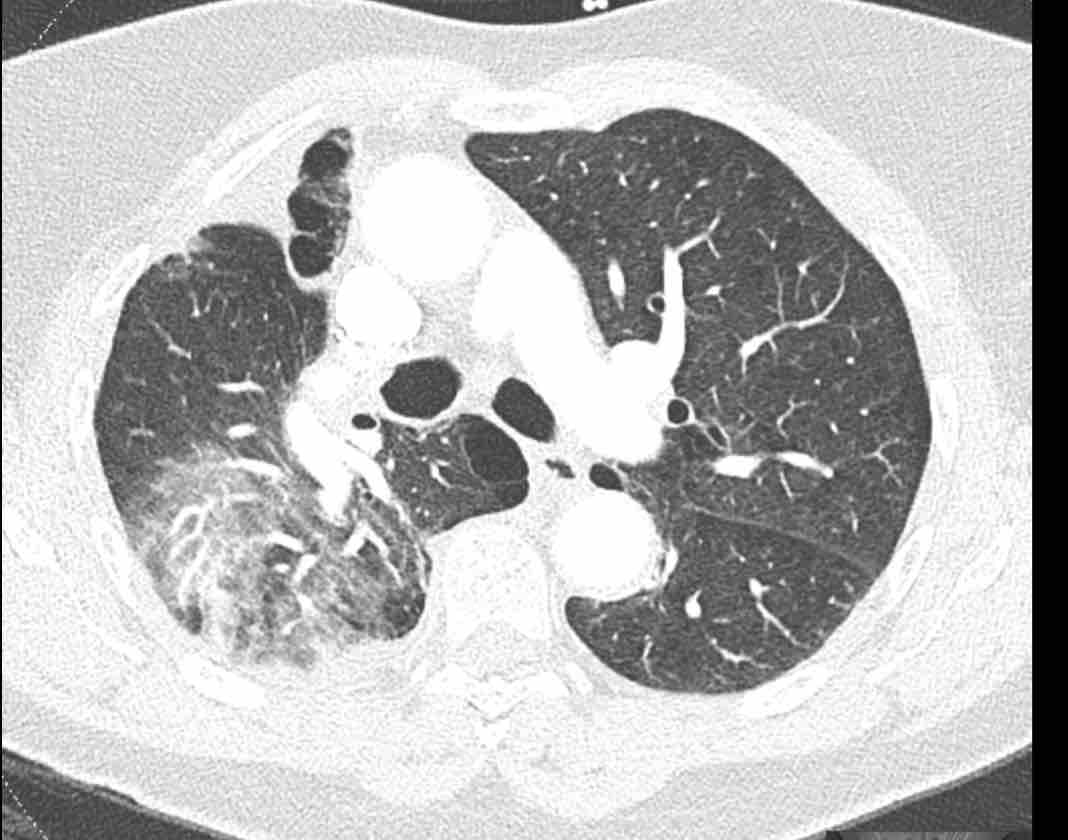

Hình ảnh

Cuộn qua các hình ảnh.

Theo dõi các phế quản của thùy dưới phổi trái cho thấy nhánh phân thùy đầu tiên của thùy dưới phổi trái còn thông; đó là phế quản phân thùy đỉnh.

Các ghim phẫu thuật nằm tại vị trí của các phân thùy đáy sau và đáy bên (LB9/10), vốn thường được cắt bỏ cùng nhau.

Do đó, phân thùy phổi có hình ảnh kính mờ và đông đặc phải là phân thùy đáy trước của thùy dưới phổi trái (LB8).

Động mạch phổi đến phân thùy này cũng không ngấm thuốc cản quang, và bản đồ tưới máu iốt nhấn mạnh thêm tình trạng nhồi máu.

Bệnh nhân đã được phẫu thuật lại và tiến hành cắt bỏ phân thùy bị nhồi máu, với xác nhận qua giải phẫu bệnh.